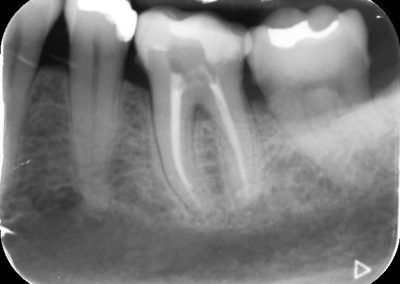

Files of different sizes are used to eliminate bacteria and infection and to shape the canals. The canals are disinfected thoroughly with irrigants and later the canals will be sealed in 3 dimensions with a special medicament called gutta-percha to prevent reinfection of the tooth and the access cavity will be sealed with a temporary filling.

After a few weeks, the tooth will be checked and when all the infection has cleared, a crown will be usually required to protect the restore the tooth to function.

Studies have shown thorough cleaning with instruments, disinfection and sealing the canals contribute to the successful healing of the infection and this success is reported as 95%.